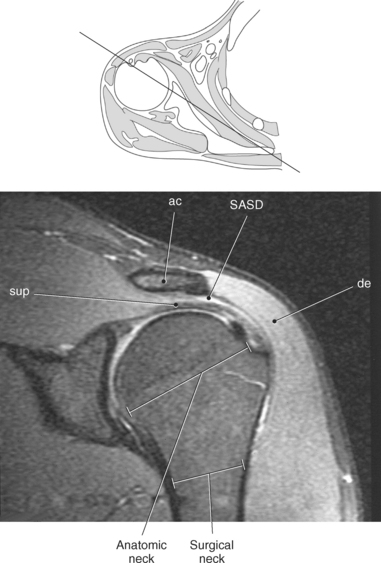

Figure 9.10 Sagittal oblique, T1-weighted MR scan of shoulder.

Key: cor, Coracoid process; cl, clavicle; sup, supraspinatus; ac, acromion; inf, infraspinatus; de, deltoid; tm, teres minor; gl, glenoid; sub, subscapularis; h, humerus; grt, greater tubercle; sc, scapula; glf, glenoid fossa; hh, humeral head.

The humerus is a long bone that articulates with the scapula superiorly and the radius and ulna inferiorly. It consists of a body or shaft, a lower end (distal end), and an upper (proximal) end (Figure 9.13). The proximal end is formed by the head of the humerus. Two tubercles project from the humeral head to provide attachment sites for tendons and ligaments. The lesser tubercle is located on the anterior surface of the humeral head, whereas the greater tubercle is located on the lateral surface of the humeral head (Figures 9.12 through 9.15). The tubercles are separated by the intertubercular (bicipital) groove, which is bounded by the crests of the lesser and greater tubercles as it descends the humerus (Figures 9.9 and 9.13 through 9.15). The humerus has two necks, the more proximal anatomic neck and the surgical neck, located inferior to the tubercles just distal to the humeral head (Figures 9.13 and 9.16). In the middle of the body or shaft of the humerus, on the anterior surface, is the roughened area of the deltoid tuberosity that gives attachment for the deltoid muscle (Figure 9.13).